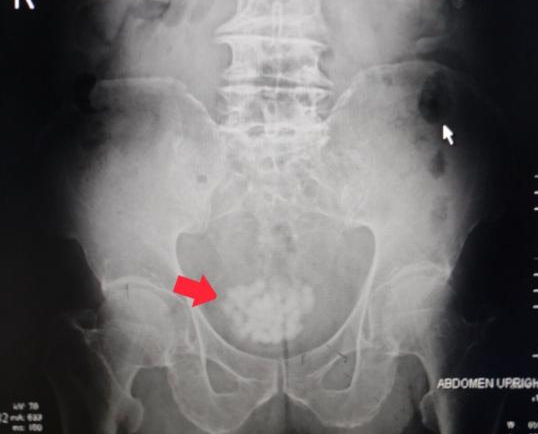

(膀胱内大量结石)

检查发现,李嗲嗲的膀胱里面已经长满了结石,前列腺达到了68x61x54毫米,属于极重度前列腺增生。